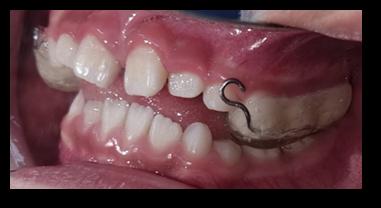

Sinodoncia vs esquizodoncia, reto diagnóstico para el odontólogo synodontics vs skizodontics, a diagnostic challenge for the dentistry

María Liliana Ríos Antezana, Carmen Adriana Blanco Lafuente

Intervención temprana en el tratamiento de la maloclusión clase III: reporte de caso. Early intervention in the treatment of class III malocclusion: case report.

Judith Mollo, Joaquín Parrado, Abner Gutiérrez......................................................................................54-62